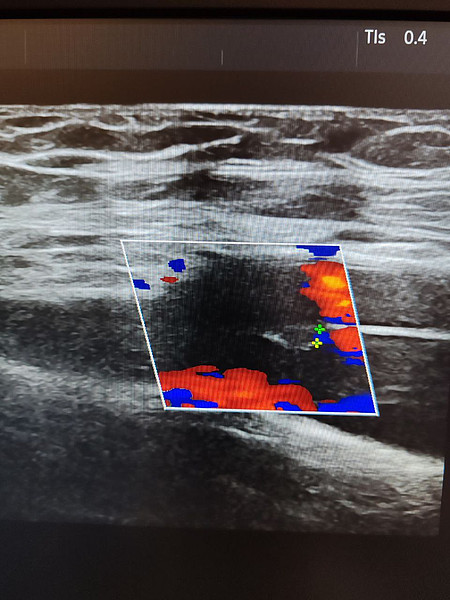

фистула 1.